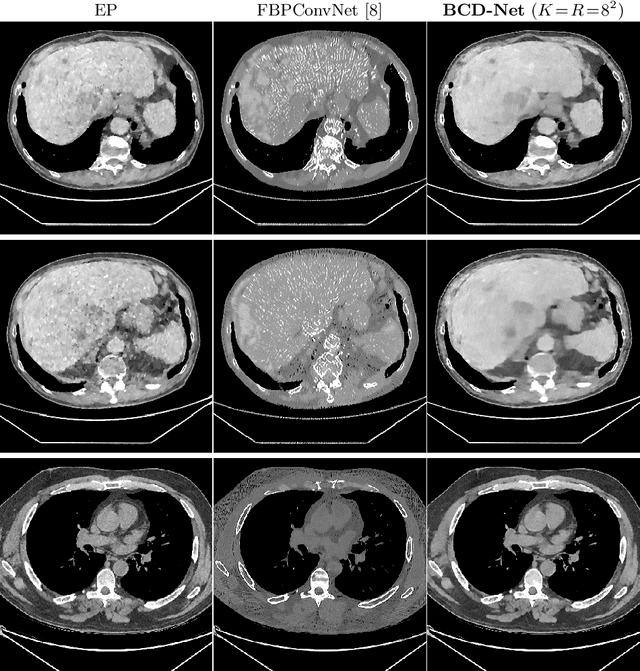

Abstract:Obtaining accurate and reliable images from low-dose computed tomography (CT) is challenging. Regression convolutional neural network (CNN) models that are learned from training data are increasingly gaining attention in low-dose CT reconstruction. This paper modifies the architecture of an iterative regression CNN, BCD-Net, for fast, stable, and accurate low-dose CT reconstruction, and presents the convergence property of the modified BCD-Net. Numerical results with phantom data show that applying faster numerical solvers to model-based image reconstruction (MBIR) modules of BCD-Net leads to faster and more accurate BCD-Net; BCD-Net significantly improves the reconstruction accuracy, compared to the state-of-the-art MBIR method using learned transforms; BCD-Net achieves better image quality, compared to a state-of-the-art iterative NN architecture, ADMM-Net. Numerical results with clinical data show that BCD-Net generalizes significantly better than a state-of-the-art deep (non-iterative) regression NN, FBPConvNet, that lacks MBIR modules.